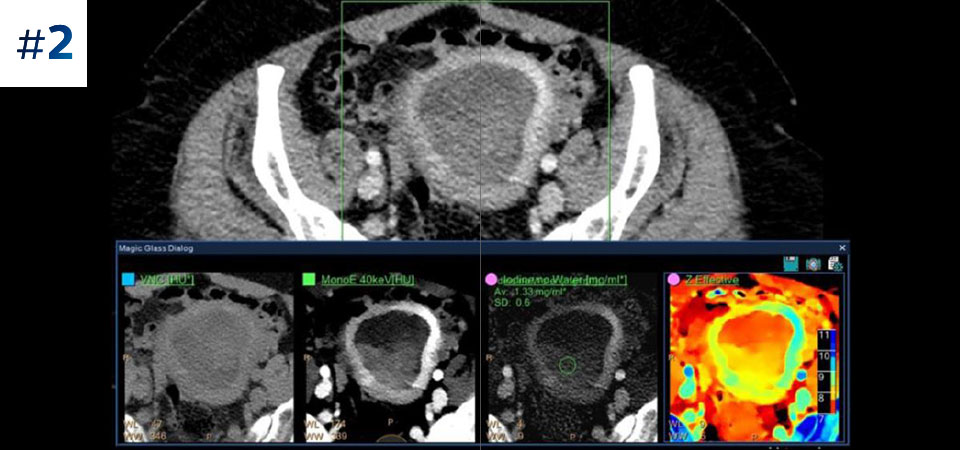

With detector-based spectral, you acquire multiple layers of data—conventional and spectral—within a single exposure and without special scan modes for improved tissue characterization and visualization.

Scan as usual A single scan for fast, low-dose conventional and spectral data for every patient, every time.

Always available 100% spectral, 100% of the time for results that are always available on-demand, even retrospectively.

Reduced follow-up exams Improved tissue characterization and visualization may reduce the need for follow-up scanning for sub-optimal exams and incidental findings.

Across patient types Benefits a wide range of patient types from pediatric to bariatric.